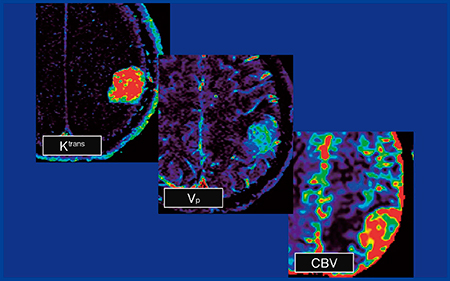

症例3(図3)の腫瘍は明瞭に造影されたが,血管が脳表面にあり腫瘍内側に皮質が認められなかったことからintraと判断され,glioblastomaが疑われた。しかし,permeabilityでは非常に高いKtransを示し,CBVも上昇が認められ,meningiomaと診断された。

図3 症例3:meningioma